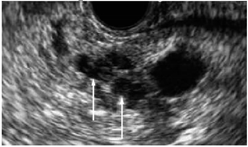

Computed tomography (CT)![]() | High sensitivity and specificity (76–92% and 67% respectively) Standardized available protocol- pancreatic protocol CT Multidetector CT Good spatial and temporal resolution Lower cost and greater availability | Radiation exposure with the risk of secondary cancer attributable to the CT procedure Performance depends on ability to administer intravenous Iodine contrast Allergies to CT contrast agents (common) Cannot detect iso-attenuating PDACs with indistinct borders and small pancreatic tumours |

Endoscopic ultrasound (EUS)![]() | High sensitivity and specificity (72% and 90% respectively) Excellent resolution for small lesions Mainly used as part of the work-up to obtain biopsy (FNA) for tissue diagnosis | Performance varies by disease T stage Invasive procedure, not practical for routine follow-up Not readily accessible imaging modality Highly dependent on technical skill of the operator Limitations for evaluating solid pancreatic lesions Procedural risks |

Magnetic resonance imaging (MRI)![]() | Highest sensitivity and specificity (93% and 89% respectively) Better soft tissue resolution No radiation exposure Better at determining metastasis Better accuracy for assessing local involvement of a pancreatic lesion | Can be difficult to obtain in patients with claustrophobia, metal devises, or allergies to gadolinium (very rare) |